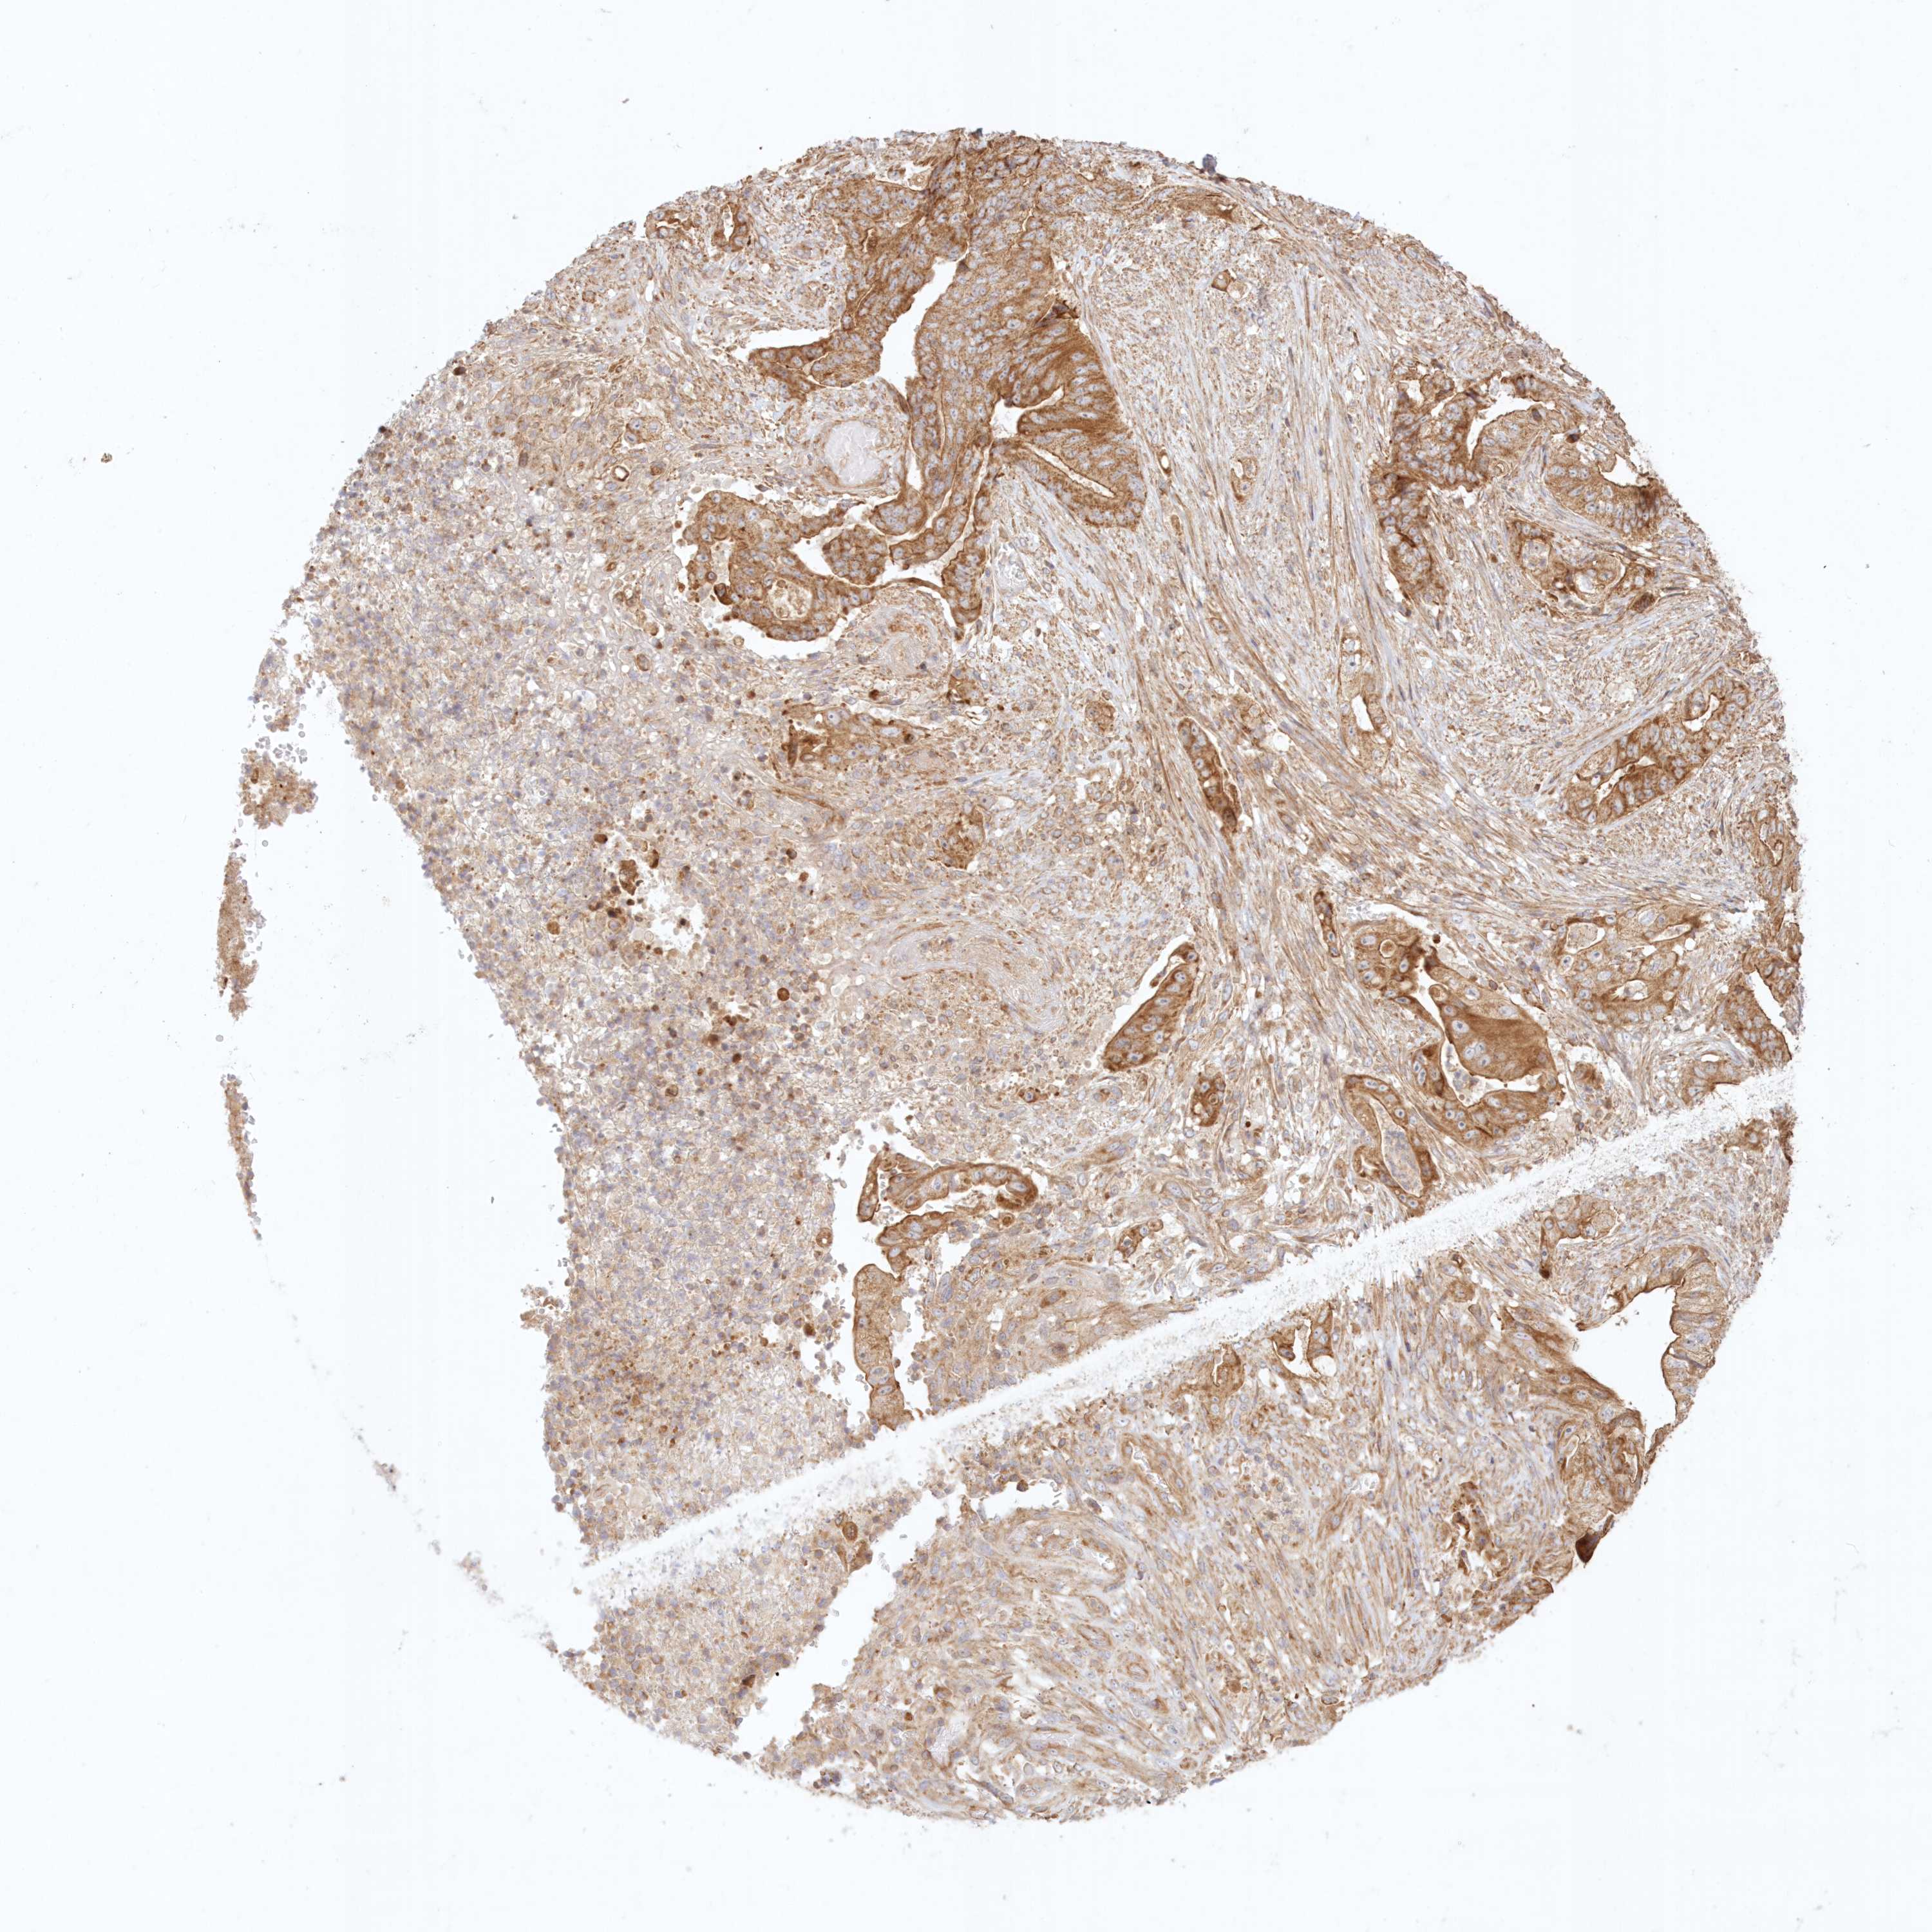

STOMACH CANCER - Protein expressioni

A mouse-over function shows sample information and annotation data. Click on an image to view it in a full screen mode. Samples can be filtered based on level of antibody staining by selecting one or several of the following categories: high, medium, low and not detected. The assay and annotation is described here.

Note that samples used for immunohistochemistry by the Human Protein Atlas do not correspond to samples in the TCGA dataset.

Antibody stainingi

Antibody staining in the annotated cell types in the current human tissue is reported as not detected, low, medium, or high, based on conventional immunohistochemistry profiling in selected tissues. This score is based on the combination of the staining intensity and fraction of stained cells.

Each image is clickable and will lead to virtual microscopy that enables deeper exploration of all samples and also displays staining intensity scores, fraction scores and subcellular localization as well as patient and tissue information for each sample.

Antibody HPA036891

Antibody HPA036892

Antibody HPA061498

Staining

High

Medium

Low

Not detected

Intensity

Strong

Moderate

Weak

Negative

Quantity

>75%

75%-25%

<25%

None

Location

Nuclear

Cytoplasmic/membranous

Cytoplasmic/membranous,nuclear

Adenocarcinoma, NOS